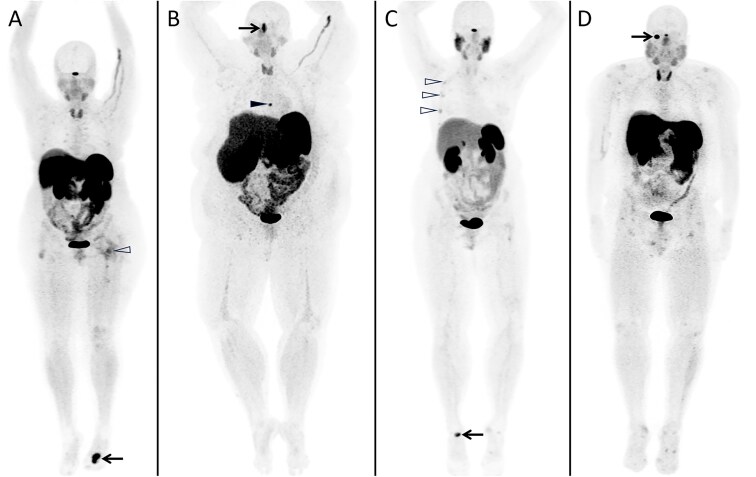

Gallium-68-DOTA-Tyr3-Octreotate (Ga-68-DOTATATE) positron emission tomography/computed tomography (PET/CT) has recently been shown to have utility for the localization of phosphaturic mesenchymal tumors (PMT) that cause tumor-induced osteomalacia (TIO), a rare renal phosphate-wasting disorder. The aim of this study was to evaluate the accuracy of Ga-68-DOTATATE PET/CT in localizing PMTs causing TIO and to compare its performance with other functional imaging modalities. Prospective recruitment and retrospective chart review of 30 patients with suspected TIO and evaluation with Ga-68-DOTATATE PET/CT between 2017 and 2023 were conducted at a tertiary medical center. True positive (TP) lesions were defined by histological confirmation of PMT. There were 22 TP lesions identified among 18 patients, with a mean SUVmax of 16.8 (±10.9). Sensitivity, specificity, and accuracy of Ga-68-DOTATATE PET/CT were 85.7%, 77.8%, and 83.3% on patient-based analysis, and 84.6%, 56.3%, and 73.8% on lesion-based analysis. Lesions such as subacute fractures, parathyroid adenomas, thymus uptake, vertebral hemangiomas, bone enchondromas, liver hemangiomas, and avascular necrosis were some of the pitfalls in interpretation. Ga-68-DOTATATE PET/CT led to a significant impact on clinical management in 24 (80%) of patients. The presence of DOTATATE-avid fractures was significantly associated with a localizing scan on univariable (OR 15.0, 95% CI 2.80-110, p = .001) and multivariable analysis (OR 9.45, 95% CI 1.33-98.4, p = .003). Ga-68-DOTATATE PET/CT has good accuracy for the localization of TIO, with superior sensitivity compared to F-18-FDG PET/CT. This significantly impacted clinical treatment decisions. Although DOTATATE-avid fractures may be a source of false positives, they may also indicate a higher probability of a localizing study.